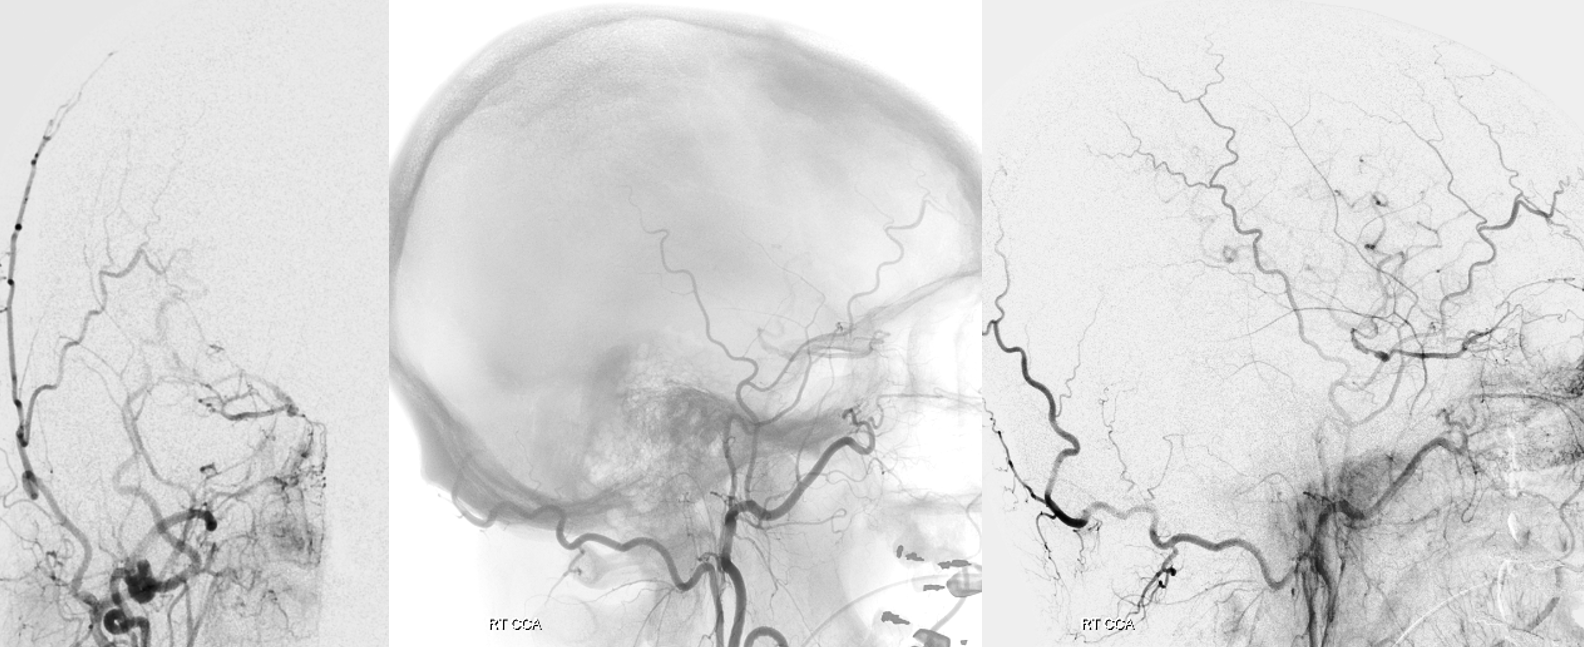

Spins are good

A secondary reconstruction and detailed analysis is better. What does arrow point to?

Spin

A better unsubtracted spin

STA-MCA bypass, right ophthalmic, and right PCOM not enough to supply right ACA at this stage — tested by left supraclinoid bypass — what is the rationale there?